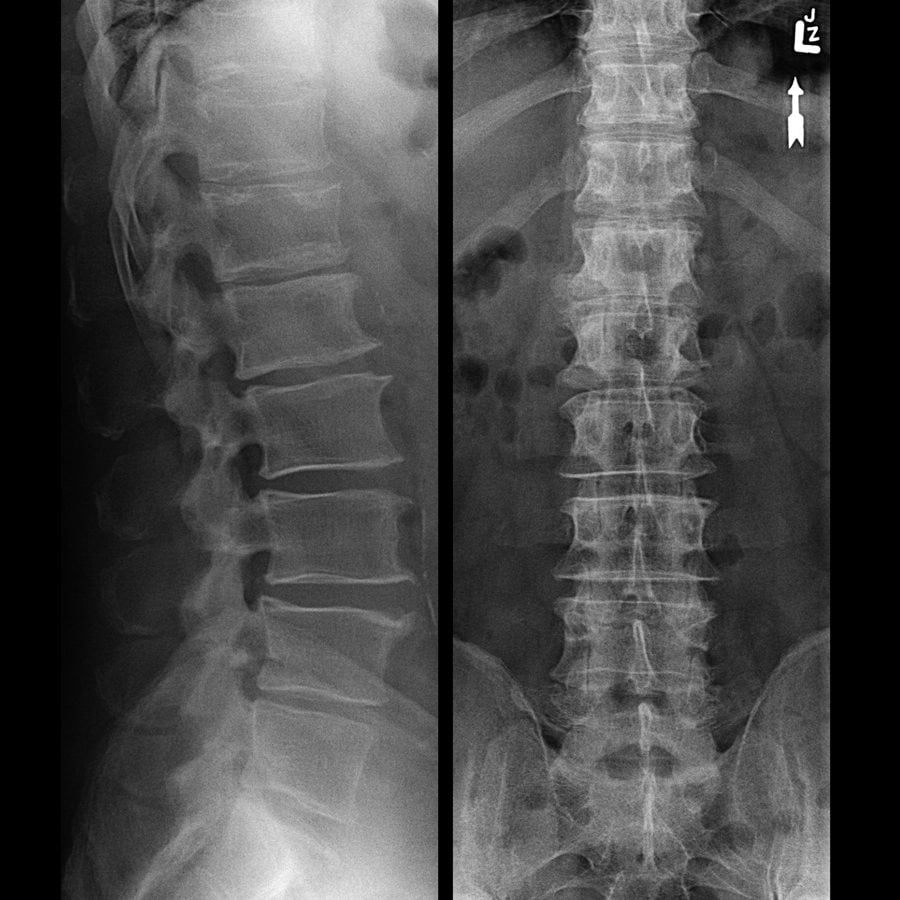

- наличие деструкции позвонков при рентгенологическом исследовании позвоночника;

Выявить патологические изменения в позвоночнике можно с помощью рентгенографии или магнитно-резонансной томографии. Первый метод является более доступным и дешевым, но малоинформативным. С его помощью выявляют только далеко зашедший остеохондроз, осложненный спондилезом. Диагностировать болезнь на ранних стадиях можно лишь благодаря МРТ, позволяющая увидеть практически любые изменения в МПД и межпозвонковых суставах.